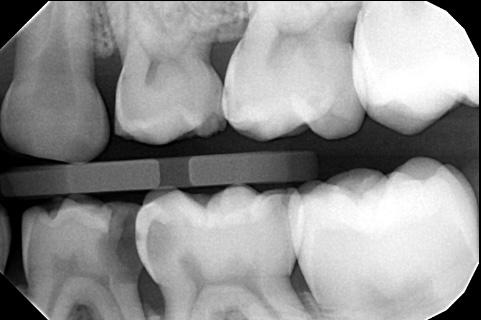

A 7-year-old male child presented to a private office for a routine exam and cleaning. Examination revealed multiple cavities, with a deep open carious lesion on the distal of #L. #L also exhibited a fluctuant swelling on the buccal gingiva near the furcation (Figure 1). A bitewing radiograph showed an apparent carious exposure in #L (Figure 2), and a panoramic radiograph suggested incipient bone loss in the furca (Figure 3). Extraction was considered, but since

an endodontist was available in the practice, a consult was scheduled to see if the tooth was salvageable. The endodontist decided to try to save the tooth at the time of the consultation.